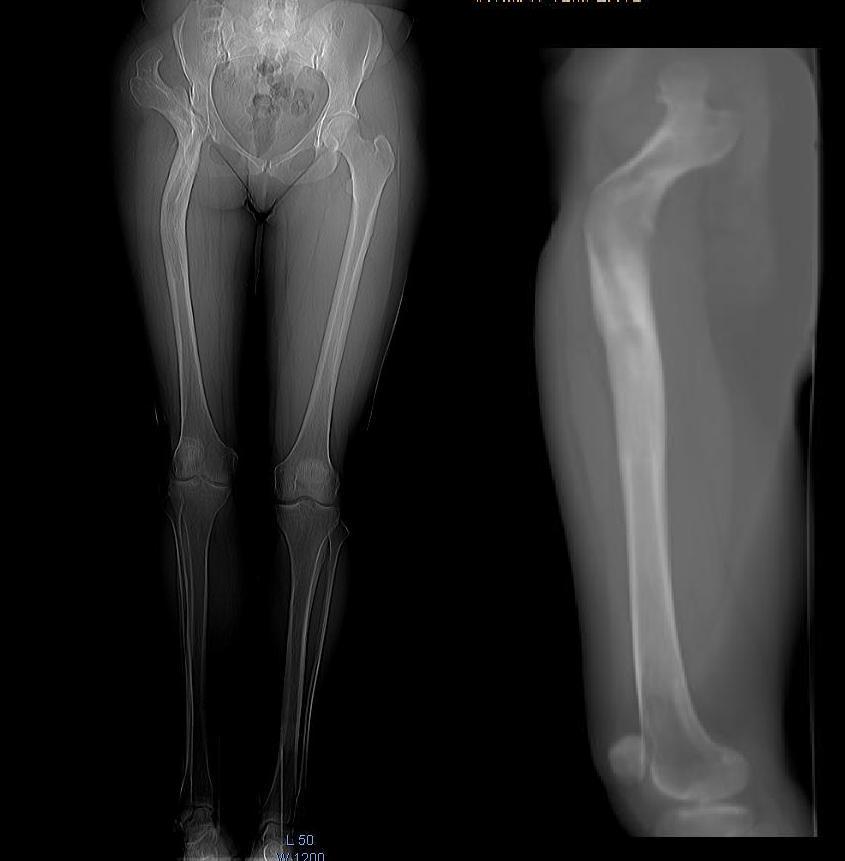

Пациентка 41 год, нормального телосложения, правосторонний диспластический коксартроз Crowe IV состояние после опорной остеотомии по Илизарову более 20-ти лет назад. Жалобы на боль в паху, пояснице, ограничение движений, хромоту. Относительное укорочение правой н.к. 2-3 см. Абсолютное периудлинение правого бедра 5-6 см (по данным КТ). Планируем укорачивающую резекцию бедра с транспозицией большого вертела. В литературе широко описаны аналогичные случаи эндопротезирования после остеотомии по Schanz, однако в отличие от Илизаровской остеотомии, без абсолютного переудлинения бедра и без деформаций канала на уровне с/3 диафиза. Ув. коллеги кто сталкивался с подобными случаями? Будем рады техническим и тактическим советам.

К сожалению у нас в наличии нет ножек Вагнера. Поэтому в отделении при тяжелых дисплазиях мы выполняли укорачивающую резекцию бедра на ножке цваймюллера. Нельзя ли в этом случае попытаться обойтись другой системой, например, Solution?